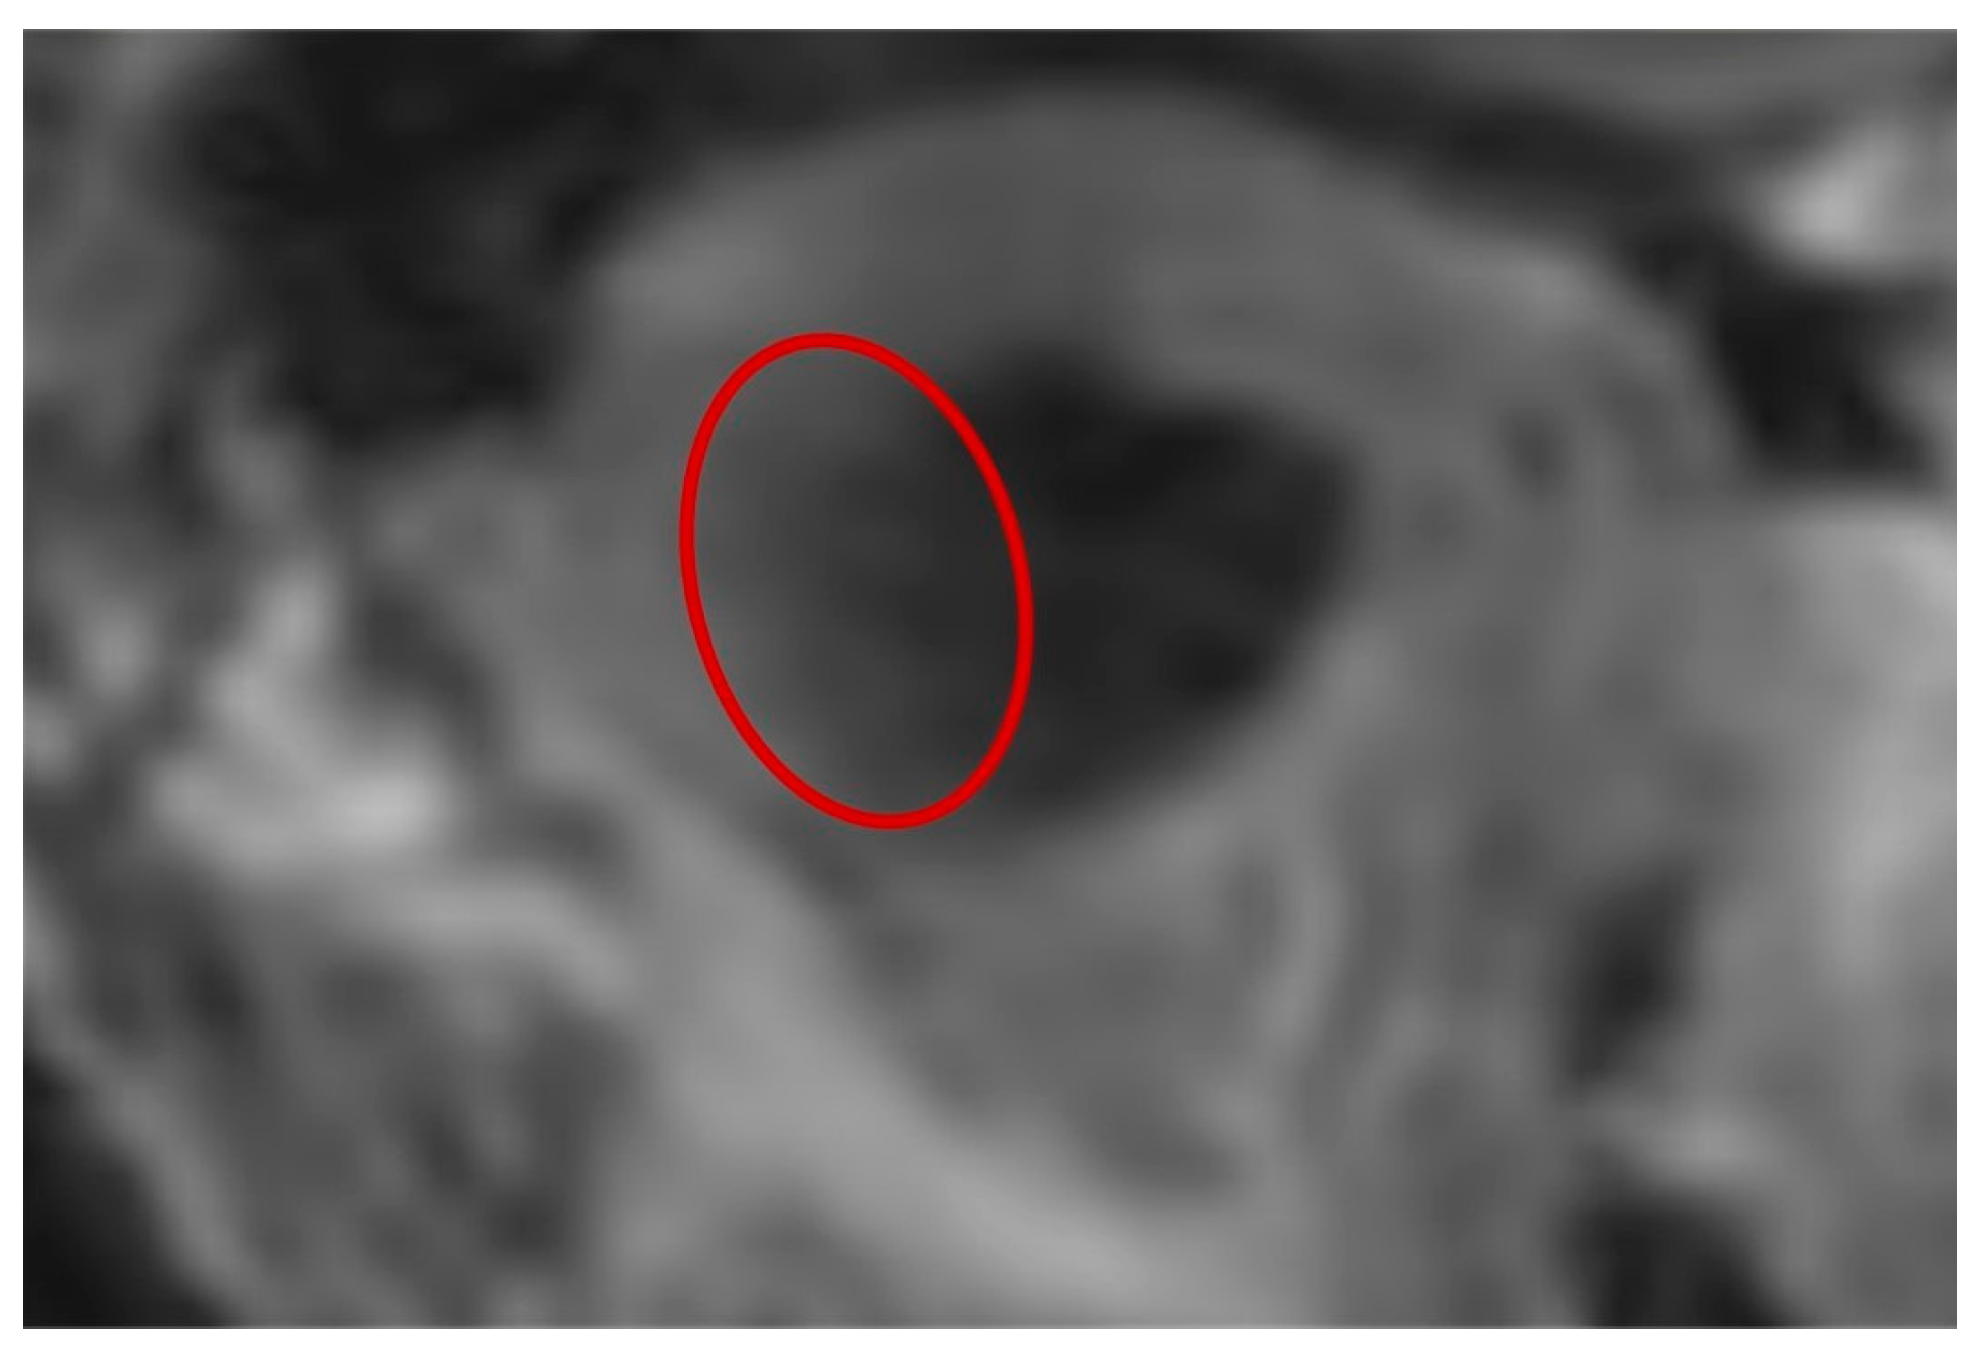

Comparing MRI models to CBCT ones, it is primarily evident that all the MRI replicates show an underestimation of both the values of S and V. This happens because the technique itself does not allow a high definition of bone structures to be achieved; therefore, the contours defined by the soft tissues that envelope condyles were used as boundaries by the operators for threshold selection [28]. This assumption, however, carries a series of shortcomings, firstly related to the information that lies at the interface between bone and soft tissues. Indeed, to exclude all the neighboring structures that are not part of the mandible but have similar Gray values on the Hounsfield scale, the experts adopted a common threshold for bone segments that considers only the pixels with small Gray values and differs from those selected for the surrounding soft tissues. However, this type of method, similar to the majority of segmentation algorithms, depends on the quality of the DICOM images processed. This aspect was particularly noticeable in zones such as the one highlighted in Figure 9 (red circle), where the slice of 3T-MRI was partly affected by noise corresponding to the interface between hard and soft tissues. This could cause a loss of information regarding the contours between the two tissues, possibly resulting in an under/overestimation of the cortical bone thickness.

Figure 9. Detail of condyle edges corresponding to the temporal zone. The red circle highlights an area on the edge between the hard and soft tissue of the condyle head, which is not well defined because it is affected by noise.